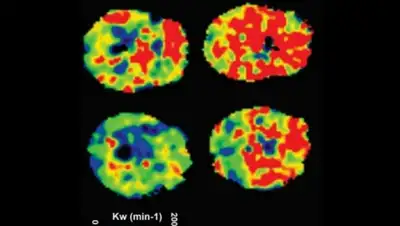

Открытие стало возможным благодаря процедуре магнитно-резонансной визуализации, в настоящее время используемой лишь несколькими исследовательскими группами во всём мире. Неинвазивная процедура использует кровь и мозговую жидкость для измерения состояния гемато-энцефалического барьера. В ходе исследования состояние девяти человек с обструктивным апноэ во сне сравнивали с состоянием десяти здоровых людей.

Исследователи обнаружили, что у пациентов, которым сравнительно недавно диагностировали обструктивное апноэ во сне (лечению они ещё не подвергались) проницаемость гемато-энцефалического барьера была значительно выше, чем у здоровых людей.

Фото Rajesh Kumar